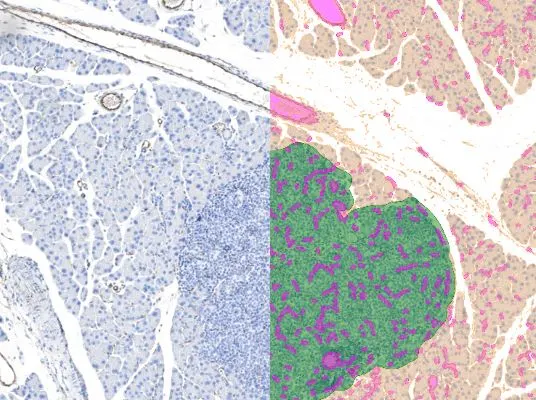

Joint TissueGnostics & PreciPoint webinar on AI-driven image analysis tools: ML-based tissue classification, deep-learning nuclei segmentation, and spatial phenotyping in stained sections.

This was a collaborative webinar series with PreciPoint GmbH focusing on AI assisted image analysis. The purpose of this webinar series is to explain AI software to new and upcoming AI users in the context of pathology research.

- How to use various types of AI models and for which research questions.